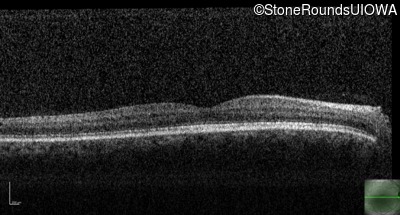

Congenital Stationary Synaptic Dysfunction (IA2g)

Congenital Stationary Synaptic Dysfunction (IA2g)

| Congenital Stationary Synaptic Dysfunction | CABP4 | Arg49Stop CGA>TGA | IVS1+1 G>T | AR |